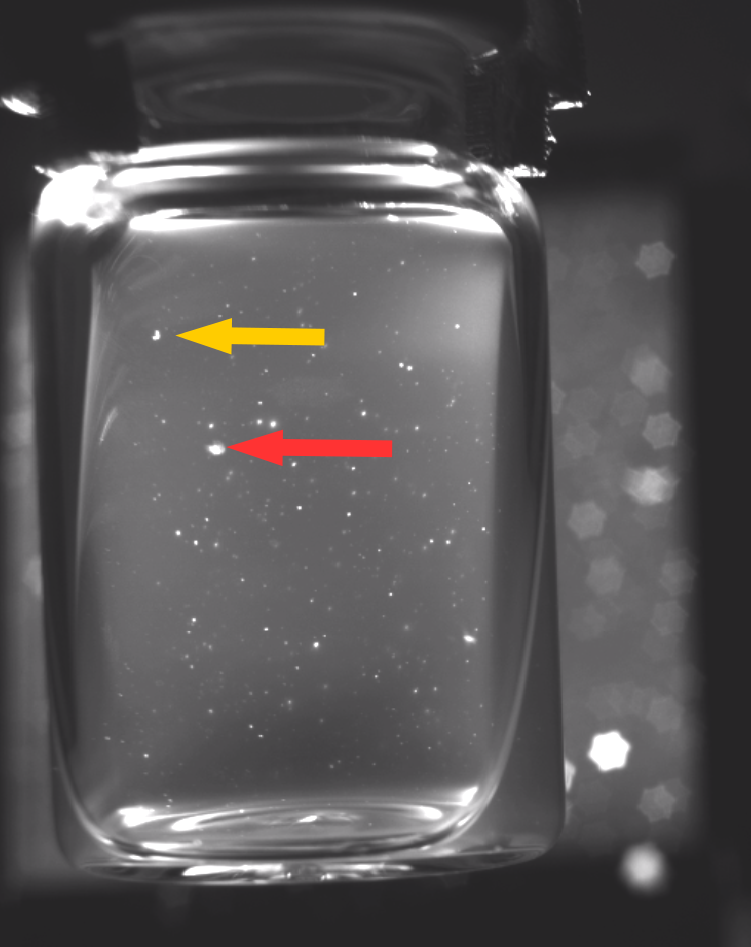

Correct lighting conditions are a prerequisite for identifying anomalies within liquid vaccines, since, due to a lack of contrast, their identification under natural lighting conditions is currently infeasible for human or automated visual inspection. A light intensity must be found that is sufficient for illuminating the vial while providing a moving contrast to identify the smallest particles [20]. To obtain a moving contrast human inspectors shake the vials to induce a swirl during manual inspections. Automated approaches meanwhile, such as the semi-automatic Seidenader V90+ inspection machine, use servo motors to stir up particles inside the vials. However, this approach has a side-effect of creating bubbles within the liquid. Furthermore, light reflections and dust particles resting on the outer surface of the vials can often be mistaken for anomalies within the liquid [20]. Opaque suspensions further increase the task difficulty by obscuring anomalies, which as a result are frequently only briefly visible. Figure 1 depicts some of these challenges.